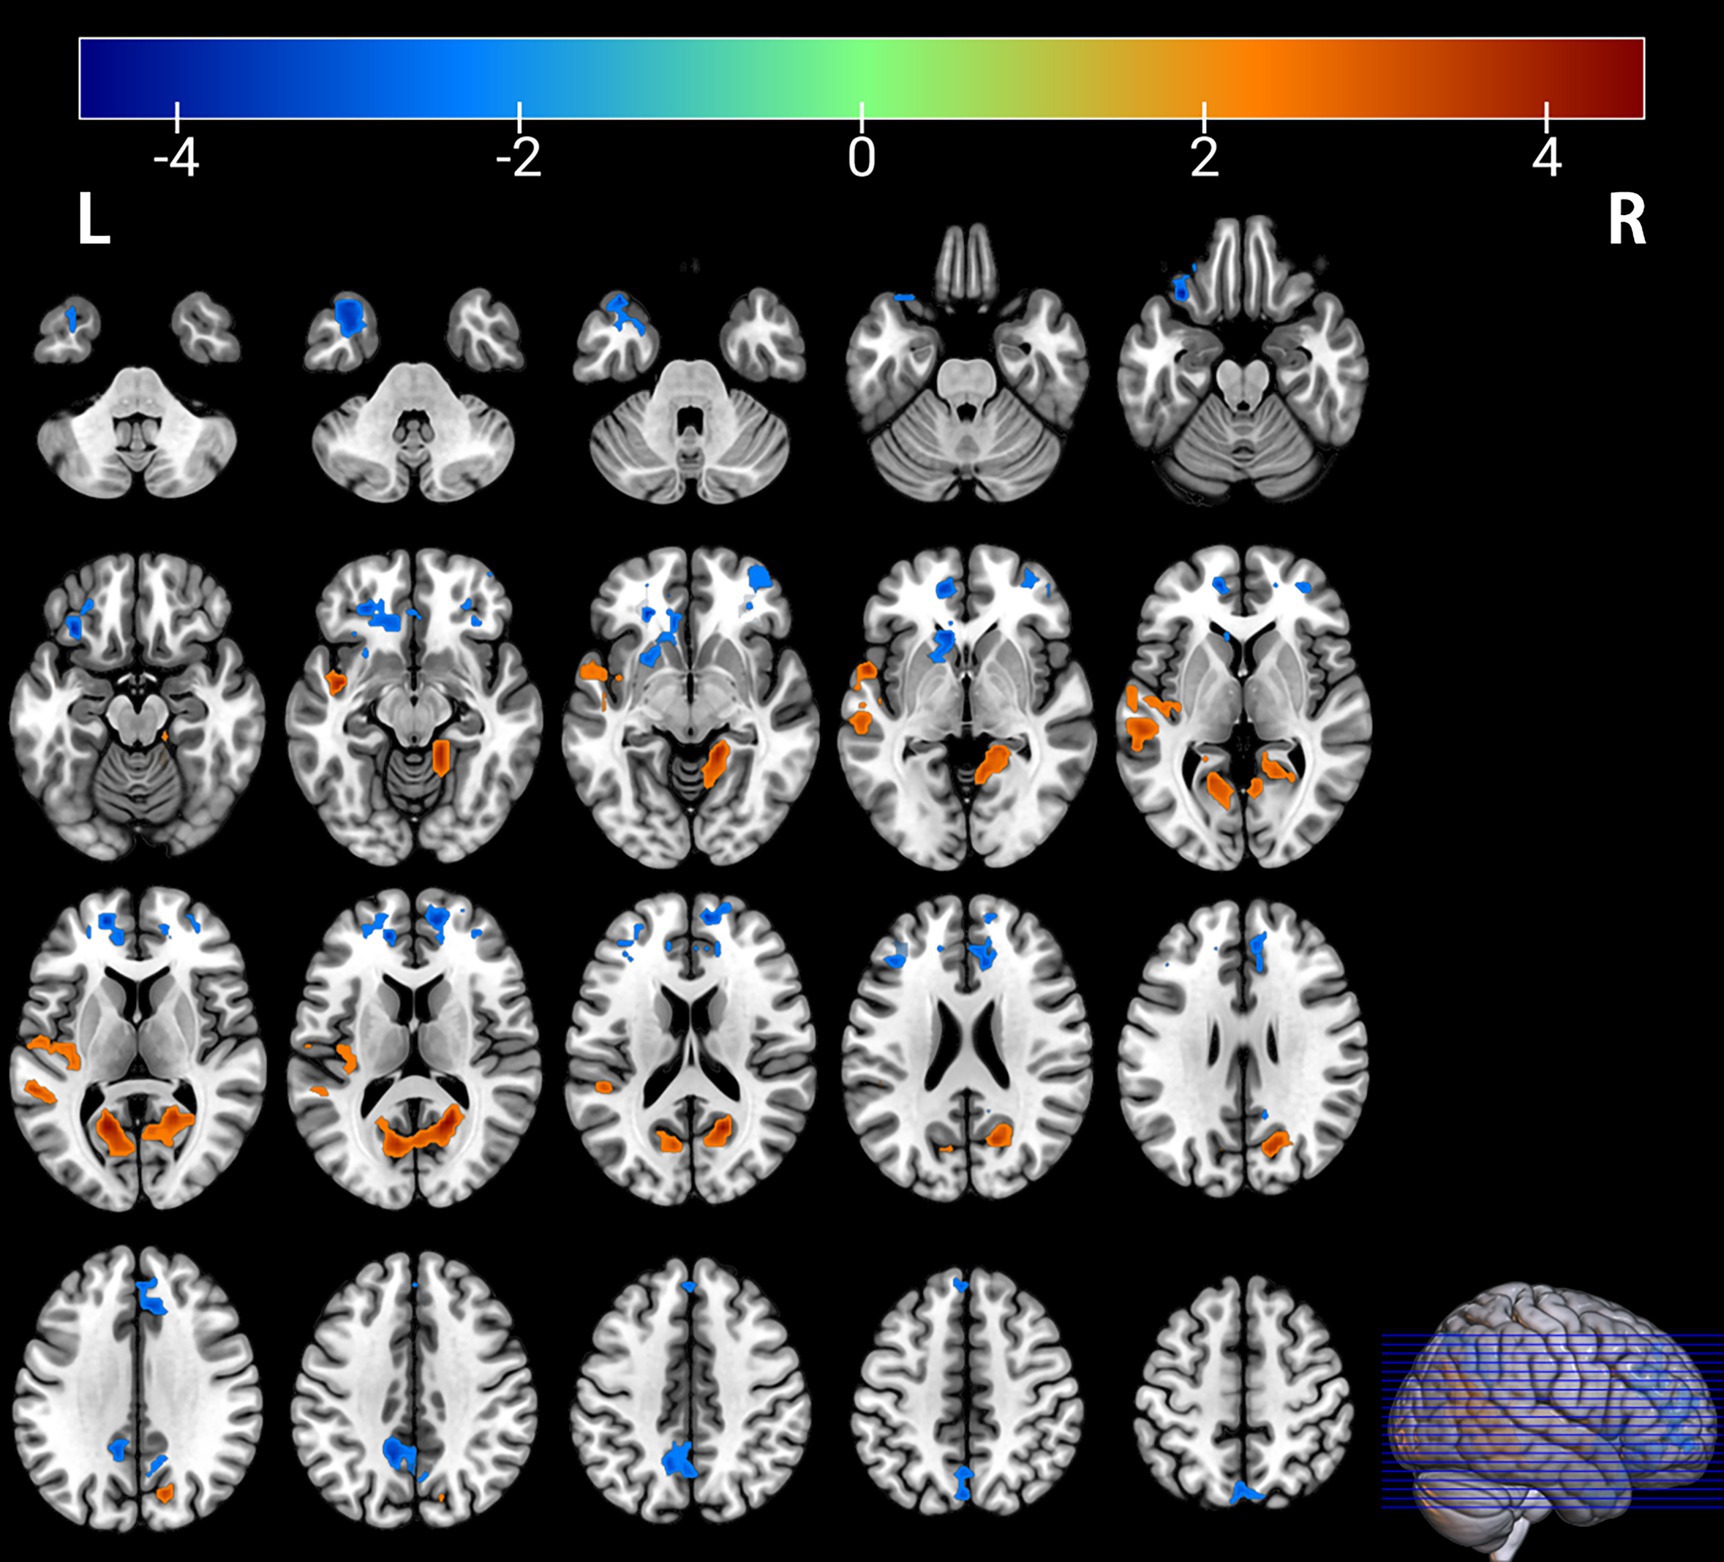

Figure 3

Brain regions with significant differences in fALFF between the PT and HC groups. The results are displayed on a 3D brain template. Statistical significance was determined by a two-sample t-test, with voxel-wise FDR correction at p < 0.05. The color bar represents the T-value. Warm colors (red) indicate a significant increase in fALFF in the PT group, and cool colors (blue) indicate a significant decrease. Significant clusters with increased fALFF include the right calcarine cortex (Calcarine_R) and left superior temporal gyrus (Temporal_Sup_L). Clusters with decreased fALFF include the left superior temporal pole (Temporal_Pole_Sup_L), right medial superior frontal gyrus (Frontal_Sup_Medial_R), left superior frontal gyrus (Frontal_Sup_L), and left precuneus (Precuneus_L). R, right; L, left.

Figure 4

Brain regions with significant differences in fALFF between the PT and HC groups. The results are displayed on 2D axial slices for detailed anatomical localization. Statistical significance was determined by a two-sample t-test, with voxel-wise FDR correction at p < 0.05. The color bar represents the T-value. Warm colors (red) indicate a significant increase in fALFF in the PT group, and cool colors (blue) indicate a significant decrease. Significant clusters with increased fALFF include the right calcarine cortex (Calcarine_R) and left superior temporal gyrus (Temporal_Sup_L). Clusters with decreased fALFF include the left superior temporal pole (Temporal_Pole_Sup_L), right medial superior frontal gyrus (Frontal_Sup_Medial_R), left superior frontal gyrus (Frontal_Sup_L), and left precuneus (Precuneus_L). R, right; L, left.

Comparison of the depressed PT group with the healthy HC group revealed differences in seven brain regions between the two groups (p < 0.05, FDR corrected, Table 3), with an increase in the Calcarine_R, Temporal_Sup_L brain regions (Figures 3, 4); and a Temporal_Pole_Sup_L, Frontal_Sup_Medial_R, Frontal_Sup_L, Precuneus_L brain regions decreased (Figures 3, 4).

Table 3

| Temporal_Pole_Sup_L (aal) | −33 | 24 | −24 | −4.4898 | 272 |

| Calcarine_R (aal) | 18 | −57 | 15 | 4.6441 | 540 |

| Temporal_Sup_L (aal) | −54 | 6 | −3 | 4.1843 | 271 |

| Frontal_Sup_Medial_R (aal) | 9 | 57 | 18 | −3.9658 | 245 |

| Frontal_Sup_L (aal) | −18 | 57 | 9 | −4.6183 | 117 |

| Precuneus_L (aal) | −12 | −51 | 36 | −4.3801 | 165 |